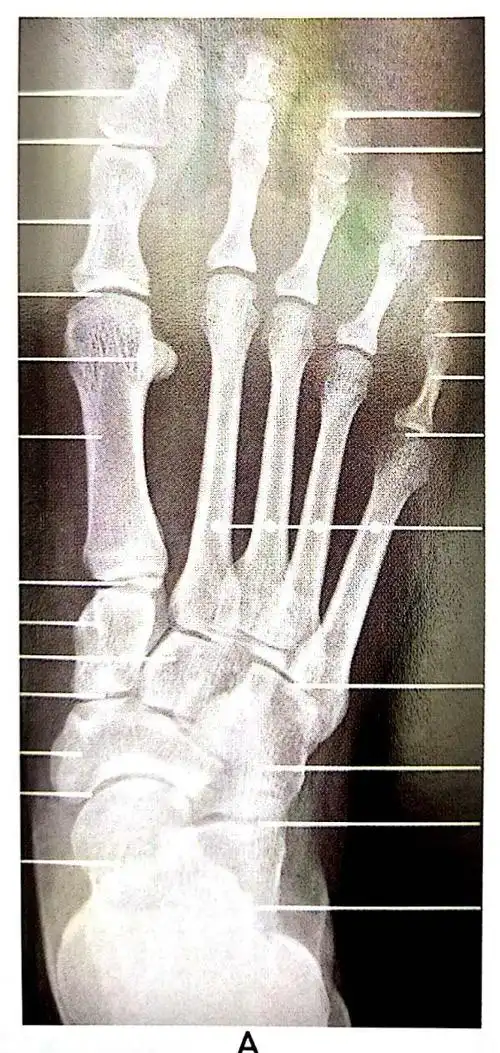

足部x线解剖(足正位片)